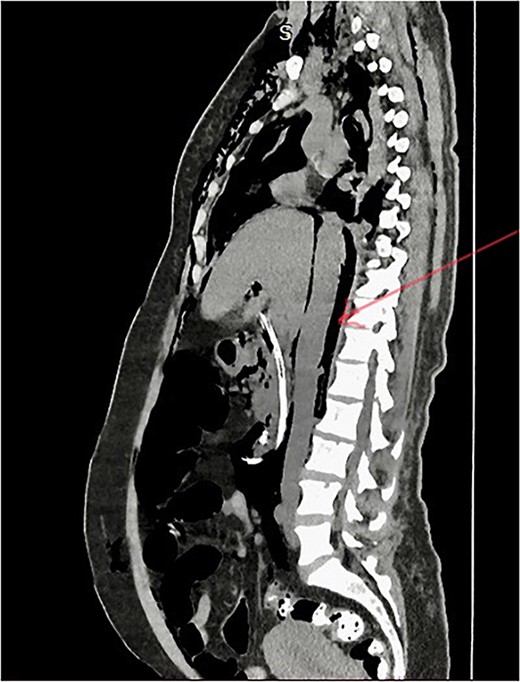

Post-ERCP NCCT abdomen shows pneumo-retroperitoneum (red arrow).

Extension of pneumo-peritoneum and subcutaneous emphysema reduced on following days. She was extubated on the third day. Oral fluid was started on day 3, and she took a regular diet on day 5. The patient’s further clinical course was uncomplicated, and she fully recovered. She was discharged on day 7. Six weeks later, laparoscopic cholecystectomy and CBD exploration with stone removal were performed, and she was discharged on post-operative day two with an uneventful recovery.

Management of ERCP-related complications depends on the type of perforation and the patient’s clinical condition. Type 1 perforations are managed with surgical repair [15]. Type 2 perforations are mainly managed conservatively, but some cases with clinical findings of peritoneal signs and sepsis and those with retroperitoneal or peritoneal fluid on CT require surgical repair [15]. Type 3 perforations are usually managed conservatively. Type 4 perforations are also generally managed conservatively, as these are no actual perforations [6, 14] In this case, the patient developed surgical emphysema and abdominal distention suggestive of perforation. She developed respiratory compromise due to pneumo-peritoneum, and her oxygen saturation was dropped during the time of procedure. Therefore, the clinical diagnosis of perforation was made, and the patient was intubated and managed conservatively in the ICU during the post-ERCP period without any need for surgical perforation repair. Post-ERCP, NCCT showed extensive pneumo-peritoneum and retroperitoneal gas with surgical emphysema.